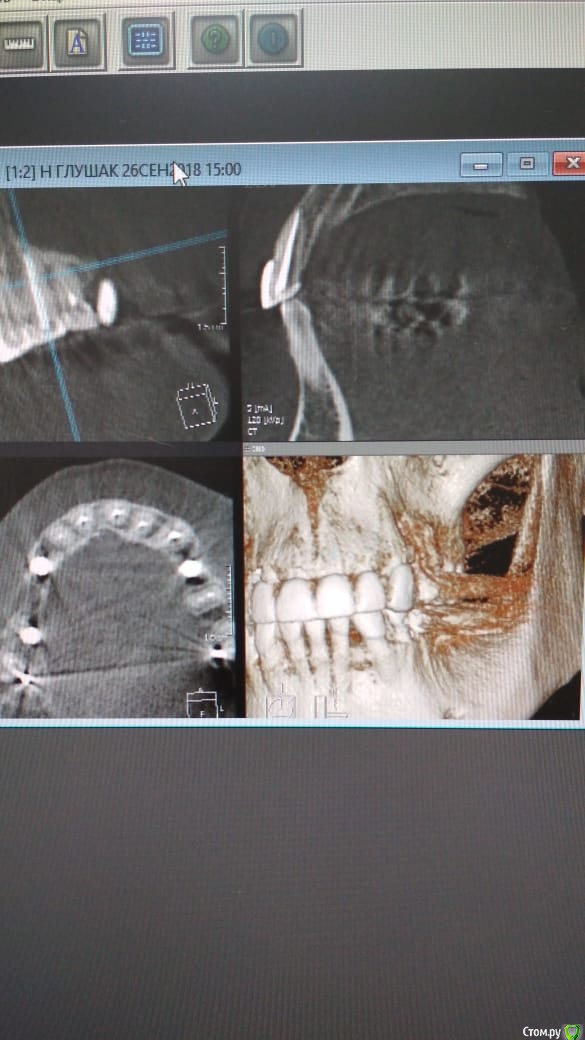

Alexandr_doc Опубликовано 26 сентября, 2018 Автор Поделиться Опубликовано 26 сентября, 2018 Прошу извинить за задержку. Прикладываю срезы со свежего КТ. Поступили предложения о хир удлинении, на мой взгляд это в данной ситуации очень рискованно. Ссылка на комментарий

kramer Опубликовано 26 сентября, 2018 Поделиться Опубликовано 26 сентября, 2018 Может, прозвучит банально, но нет смысла резцы вывести из окклюзии? По КТ плотный контакт с антагонистами Ссылка на комментарий

Alexandr_doc Опубликовано 21 сентября, 2018 Автор Поделиться Опубликовано 21 сентября, 2018 Точно ли на кт нет изменений на корнях зубов? Мне на рентгеновских снимках что-то видится. жесткая каппа на верхний зубной ряд - я бы начал с этого.Нижние резцы устойчивы?Чем вам не нравится глубокая поддесневая препаровка? Десна выглядит также как и на интактных зубах НЧ.Как проверяется работа на предмет локальной перегрузки - не знаю, расскажите пожалуйста.На кт изменений нет, мне хотелось их найти, но нет. Мне будет не сложно сделать срезы и приложить их к посту, рассматривал некачественное эндо как один из первых причинных факторов. Жесткая капа какая? Какой дизайн и схему порекомендуете? Десна действительно сейчас выглядит также как и в других участках. При гипсовке в ЦС проверены: наличие первого контакта на фронтальной группе, проверена схема направляющих, распределение контактов на моделях. Ссылка на комментарий